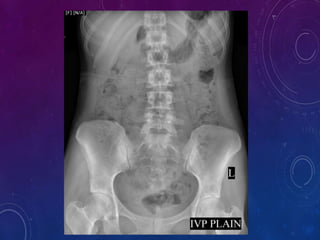

 A scout film is taken including the Kidneys,Ureters,Bladder and Urethral

Regions on a large size film.

 Plain X-Ray KUB/Scout film -14x17

Plain X-ray KUB /Scout film provides valuable information and sometimes

indicates provable diagnosis.

Useful in assessing :

1) Calculus

2) Intestinal abnormalities

3) Intestinal gas pattern

4) Calcification

5) Abdominal mass

6) Foreign body